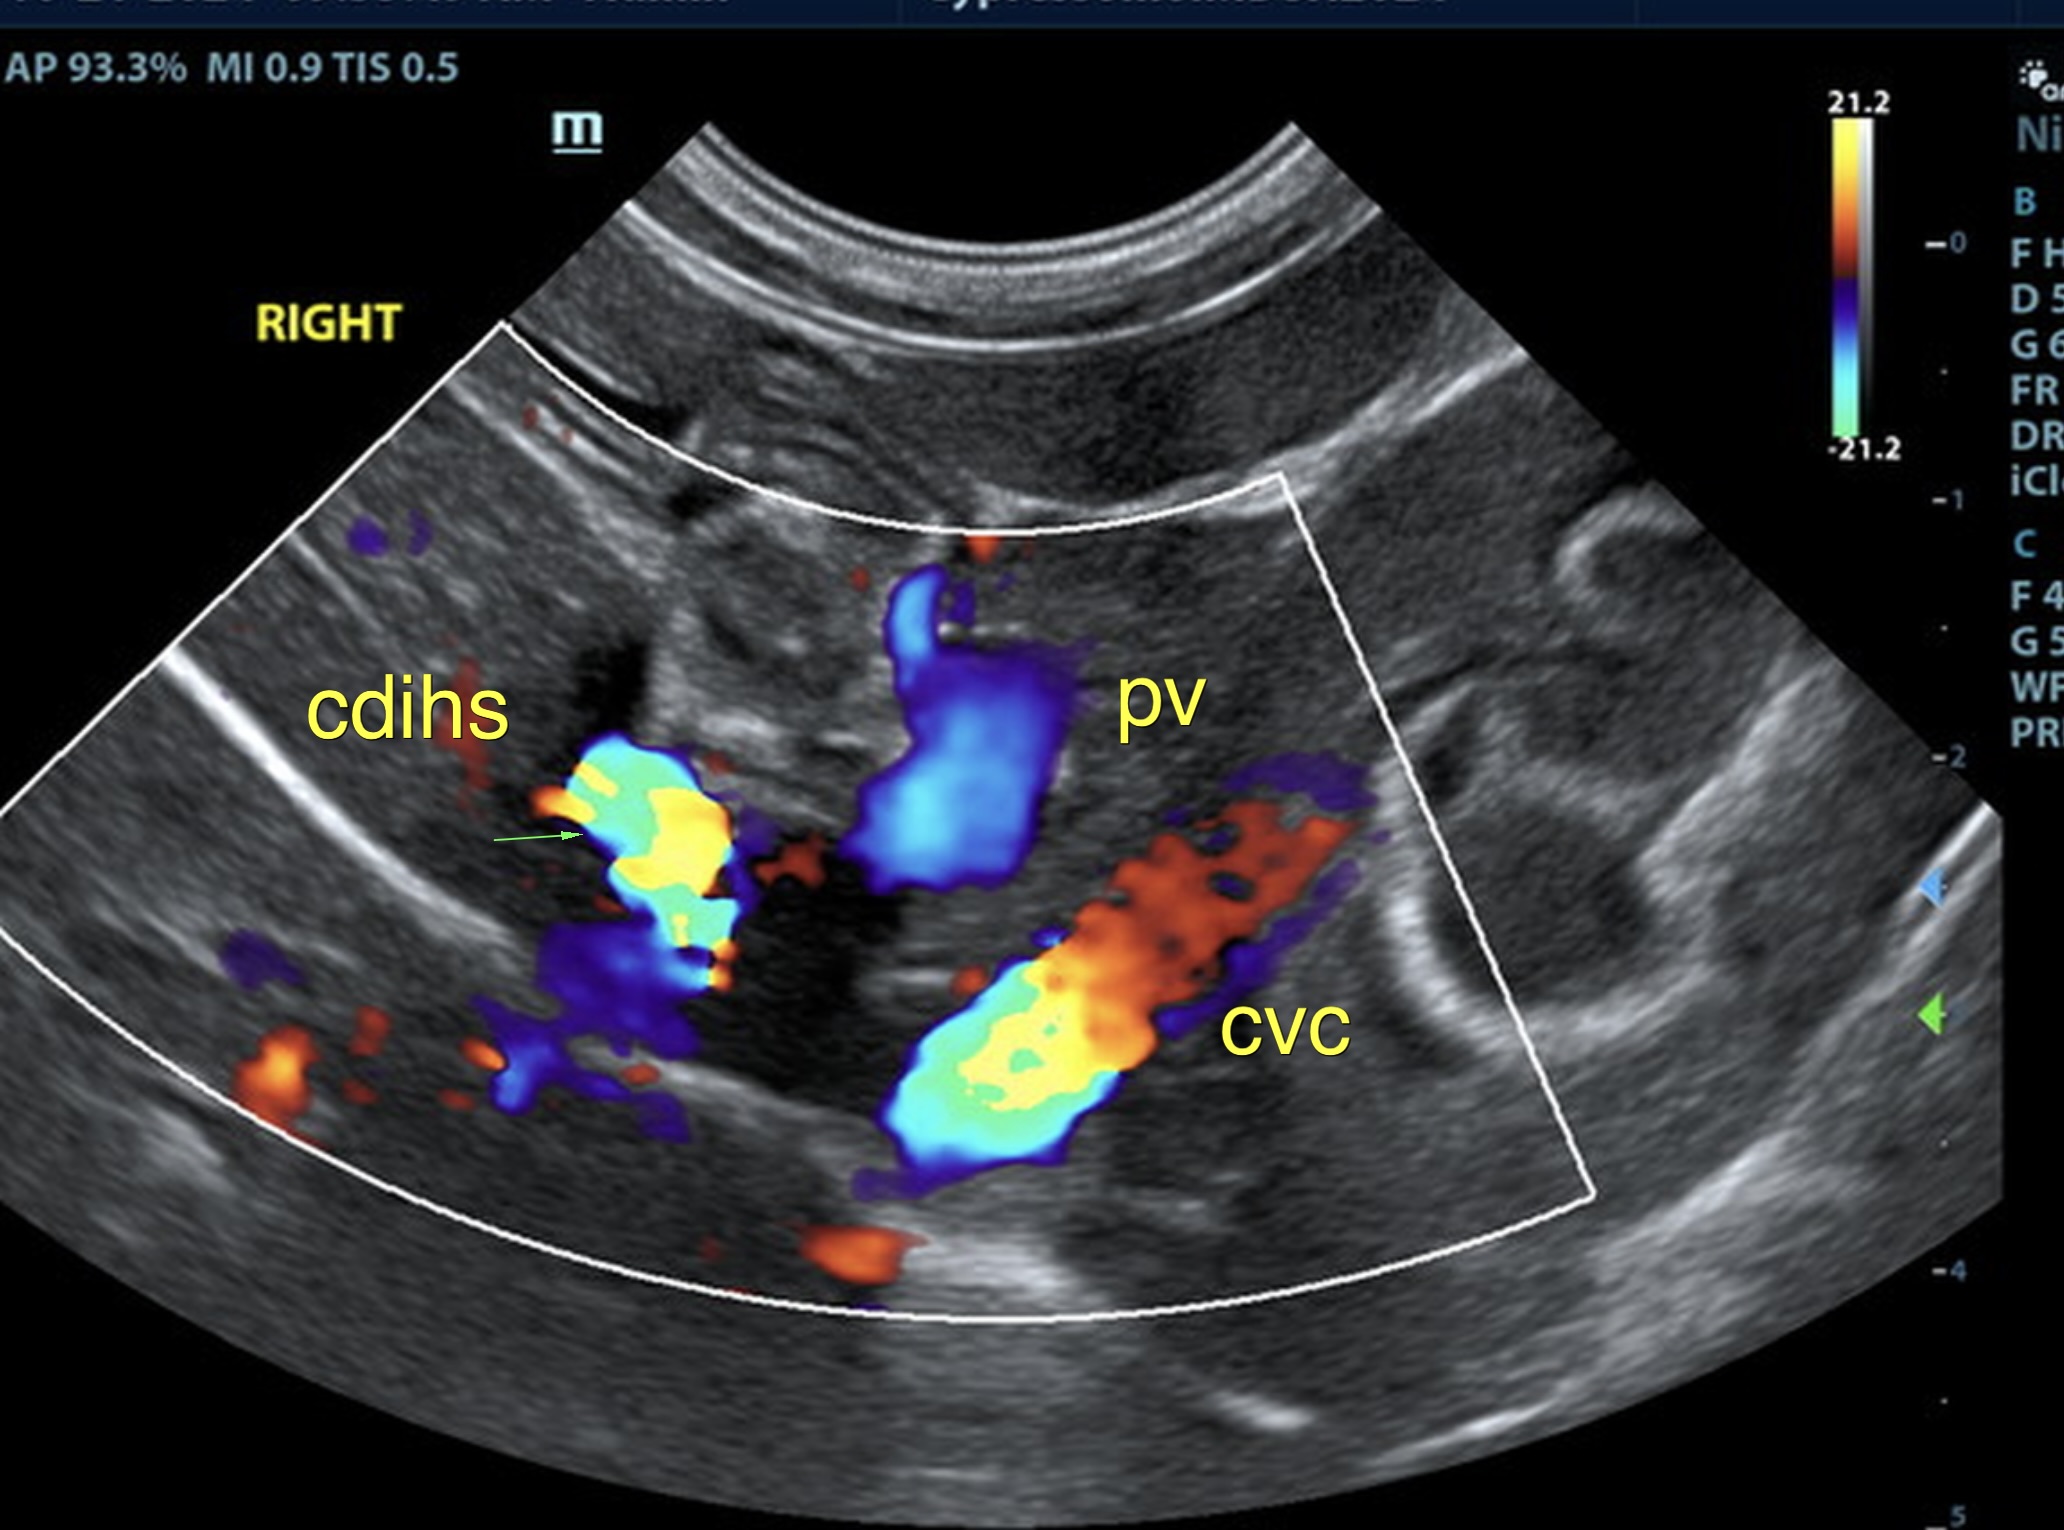

Suspect intrahepatic shunt, central divisional or right divisional.

The liver was subnormal in size, yet the portal vein and vena cava ratio was 1:1. The portal veins were subnormal in size and measured 0.34 cm. The vena cava was enlarged and measured 0.34 cm. The vena cava was enlarged and measured 0.72 cm, aorta measured 0.4 cm. The branching of the portal vein appeared to be normal and of adequate volume. The portal vein and vena cava measured 0.5 cm each in the extrahepatic space. The splenic vein entry into the portal vein and gastroduodenal vein entry into the portal vein appear to be normal. There was one turbulent vessel in the region of the central branch of the portal vein, which may represent an intrahepatic shunt, but this could not be confirmed. The width of the shunt is approximately 0.76 cm. This is in position of central divisional shunt; however, right divisional origin cannot be completely ruled out. The gallbladder presented acceptably thin walls with primarily anechoic content. The cystic and common bile ducts were normal.